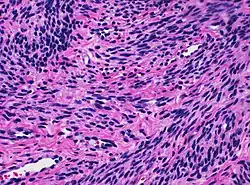

![]() Histology of myometrium | |

The myometrium is the middle layer of the uterine wall, consisting mainly of uterine smooth muscle cells (also called uterine myocytes[1]) but also of supporting stromal and vascular tissue.[2] Its main function is to induce uterine contractions.

The myometrium is located between the endometrium (the inner layer of the uterine wall) and the serosa or perimetrium (the outer uterine layer).